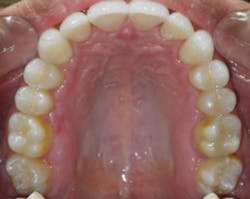

Case 2: 48-year-old female: 15-month clear aligner treatment. This case demonstrates an improvement in a remodeled alveolar complex and an increase in vertical dimension. Case and photos courtesy of Dr. Ben Miraglia.

Before: V-shaped arch. After: U-shaped arch.

Before: V-shaped arch. After: U-shaped arch; implant placed No. 14.